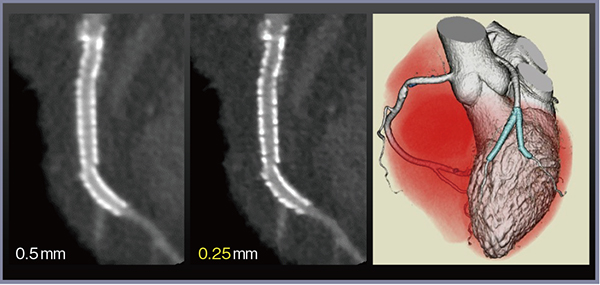

また,高精細CTは,320列Area Detector CT(ADCT)と比較し,冠動脈ステント内腔の描出能も向上している。従来の冠動脈CTでは,3mm未満の小径ステントの評価は困難とされてきたが,高精細CTのスライス厚0.25mmの画像では,2.5mm径のステントの描出能が著明に改善し,内腔の評価が可能である(図2)。

図2 高精細CTによる小径ステントの評価

対角枝 2.5mmステント